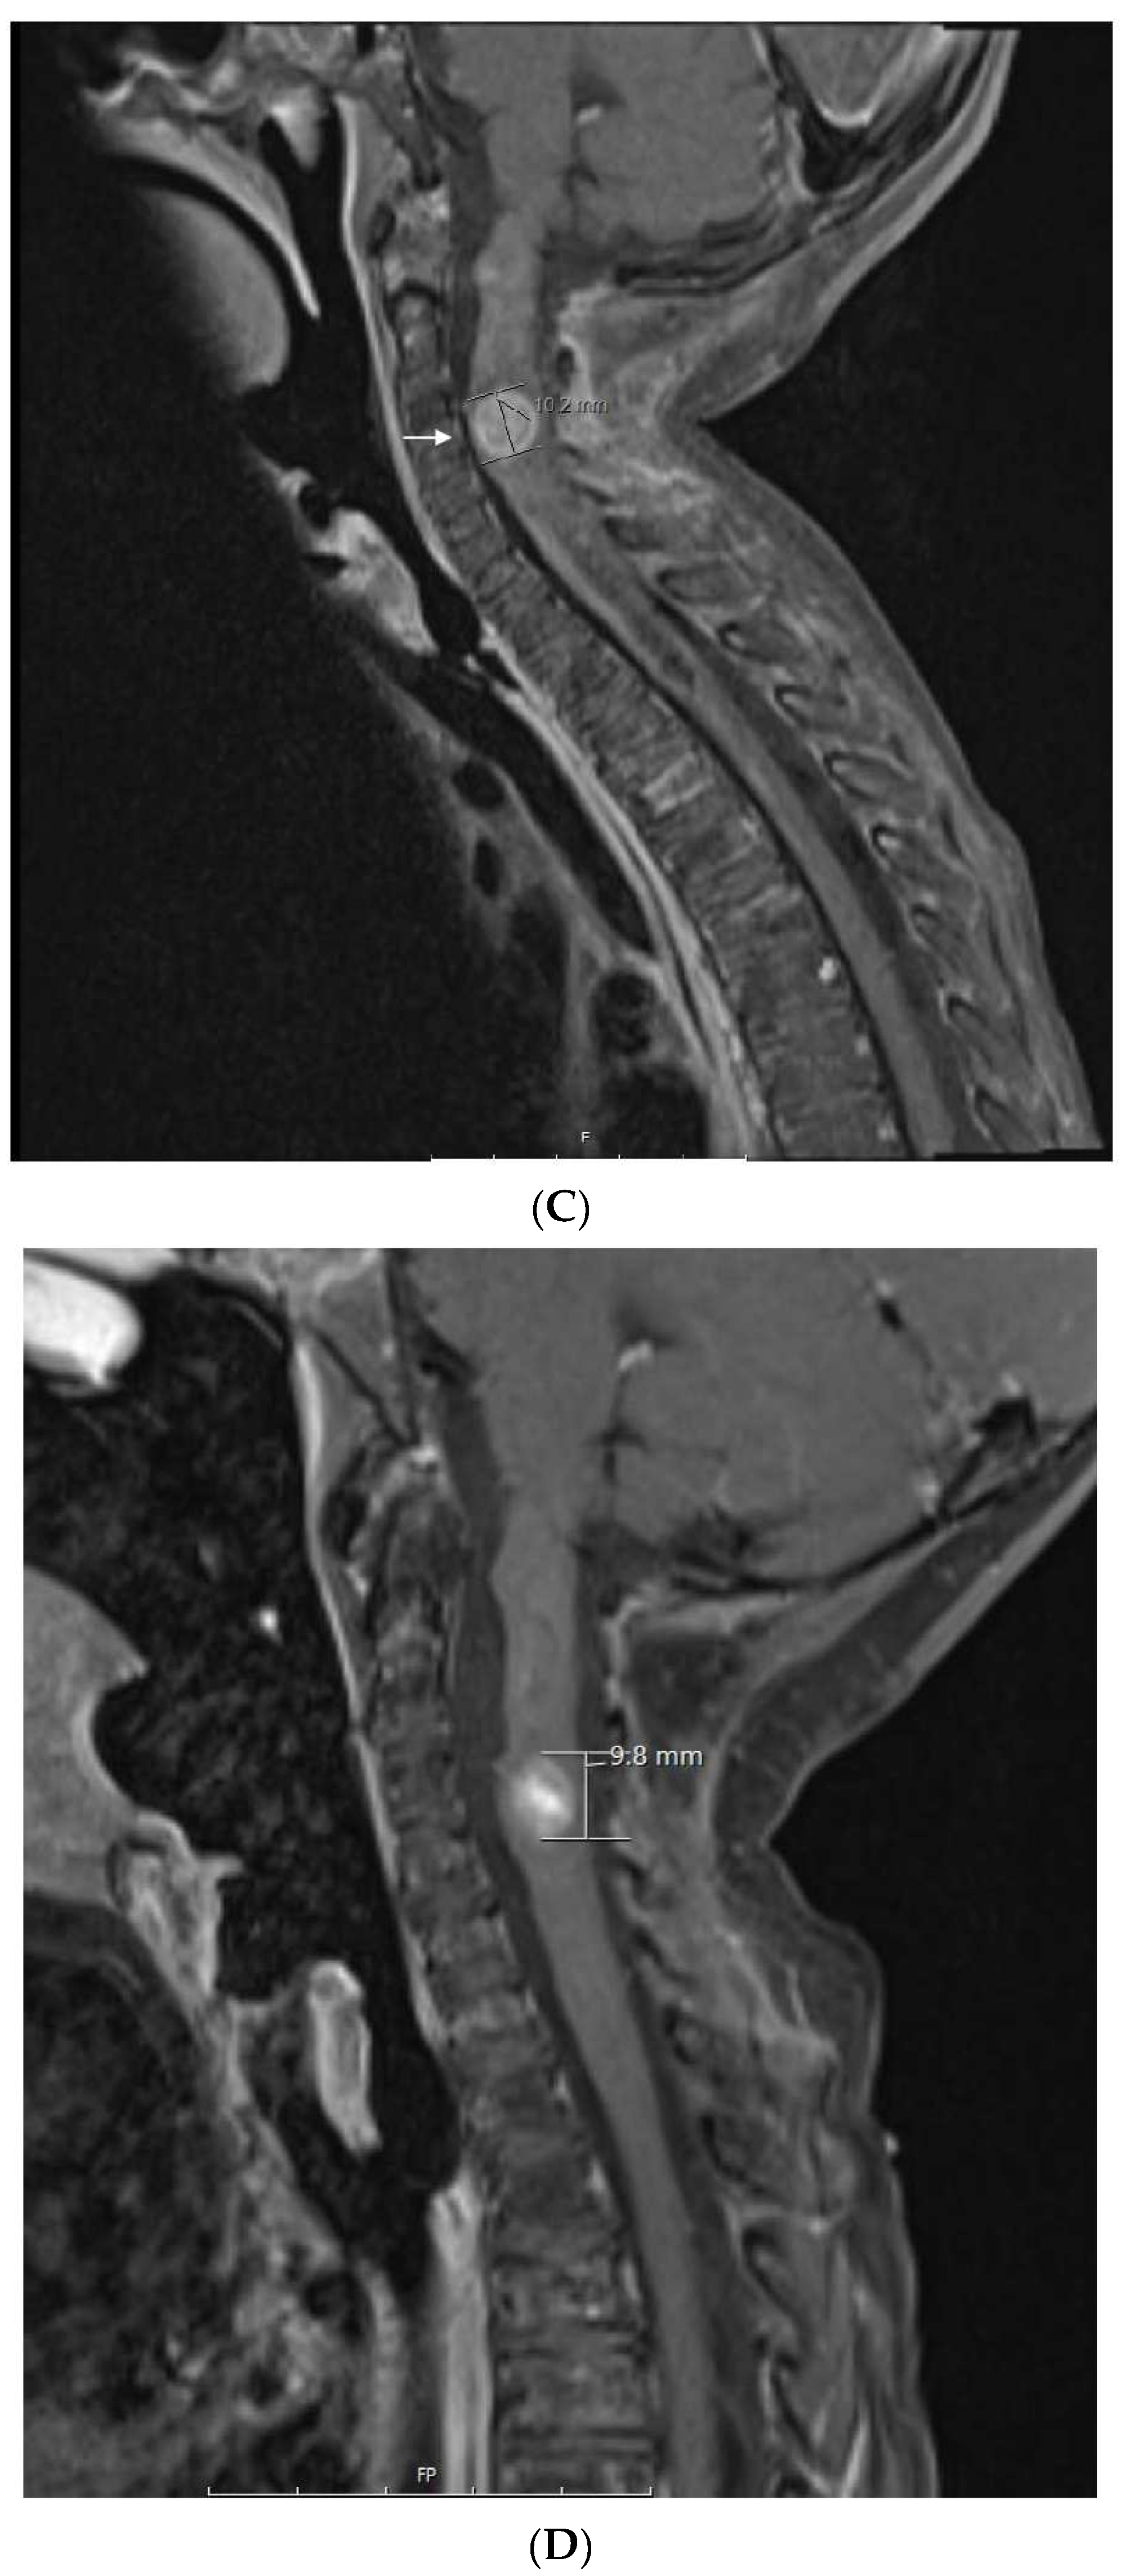

1.4. Patient 4

Patient 4 was a Hispanic girl diagnosed with localized medulloblastoma without desmoplastic or anaplastic features when she presented with headaches, emesis, and blurred vision and a 4.9 × 4 × 4.5 cm heterogeneously enhancing tumor filling the fourth ventricle with associated moderate obstructive hydrocephalus at 5 years of age. Following gross total resection of the tumor, residual linear enhancement in the tumor bed was documented. She subsequently received 2340 cGy radiation to the craniospinal axis with a 3060 cGy boost to the posterior fossa (5400 cGy total) with concomitant vincristine after surgery. This was followed by 8 months of maintenance with vincristine, cisplatin, lomustine alternating with vincristine and cyclophosphamide as per ACNS0331 [37].

Three months off therapy, she developed a first relapse (Figure 3A) with recurrent tumors in the anterior horn of the left lateral ventricle (two), posterior horn of the left lateral ventricle (one), and anterior horn of the right lateral ventricle (one). CSF showed one abnormal cell. She was treated with 7 weeks of temozolomide followed by 1400 cGy of radiation to the ventricles and Gamma Knife surgery to a residual nodule, followed by autologous peripheral blood stem-cell transplantation (PBSCT), followed by 6 months of isotretinoin.

Figure 3.

Patient 4: (A) image shows and enhancing tumor in the anterior horn of the left ventricle when she presented with first relapse of medulloblastoma. She achieved complete remission with salvage therapy; (B) image shows an enhancing tumor involving the anterior aspect and floor of the fourth ventricle (arrows) when she presented with second relapse; (C) image shows response to 3 months of metronomic therapy with decreased size and intensity of enhancing lesions; (D) image shows interval progression of the tumor seen in T2 FLAIR resulting in a change from temozolomide to etoposide at 4 months of treatment; (E) image shows resolution of the tumor mass and T2 FLAIR changes at 8 months of metronomic therapy; (F) image shows progressive disease at 10 months of treatment.

Three months later, she experienced a second relapse (Figure 3B) with a 1.7 × 1.4 × 0.5 cm enhancing tumor in the fourth ventricle, for which she was started on metronomic chemotherapy with alternating temozolomide (60 mg/m2/day; days 1–21) and CTX (30.9 mg/m2/day; days 22–42), daily celecoxib (250 mg/m2) and VA (15 mg/kg), and bevacizumab (5 mg/kg) every 3 weeks. After 3 months on metronomic chemotherapy (Figure 3C), a partial response was documented with improved enhancing lesions in the dorsal brainstem and inferior vermis. At 4 months (Figure 3D), she developed multiple cranial nerve neuropathies and heterogeneous enhancement with mild increased volume at the left midbrain at the level of the left cerebellar peduncle, for which temozolomide was changed to VP16 (24.6 mg/m2). This was complicated by hematologic toxicity requiring several treatment interruptions and VP16 dose reductions. After 8 months on treatment, MRI showed resolution of the enhancing tumor, an interval decrease in T2 changes, and diffusion restriction in the left cerebellar peduncle (Figure 3E). After 10 months on treatment (Figure 3F), she developed an extensive infiltrative tumor involving the dorsal mesencephalon, pons, and lower brainstem, and she died of her disease 2 months later. This heavily treated patient refractory to aggressive standard salvage therapy experienced 8 months of response and survived 12 months on metronomic chemotherapy.